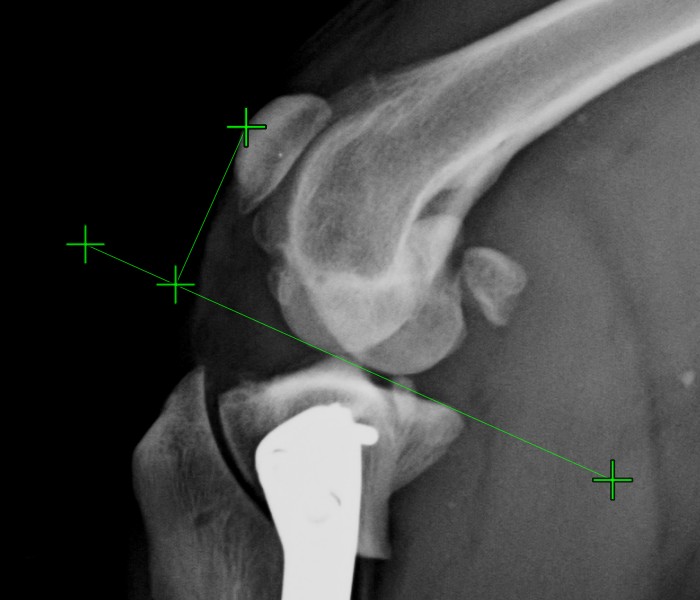

Hide/Show Measurements and Subtitles¶

The measurements and their description and subtitles can be hidden by using the Hide/Show Measurements and Subtitles button in the viewer toolbar. Depending on the active state of the measurements, the button is accordingly updated.

The button always shows the current active state of the measurements.

Change this setting individually for each measurement by using the measurement list.

All of the measurements are still visible in the viewer area, however their description and subtitles are hidden.

Additionally, the visibility of the measurements in the viewer area can be toggled by using the Menu -> Show measurements option from the Viewer menu.